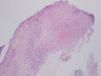

La sospecha diagnóstica inicial fue un proceso infeccioso, a nivel de la herida quirúrgica y la lesión de la pierna, por lo que se realizaron tomas para cultivo microbiológico y se inició antibioterapia empírica con amoxicilina-clavulánico 875/125 mg cada 8 horas y antiinflamatorios no esteroideos por vía oral, así como fomentos. Dos días después la paciente refería mejoría del estado general, la herida quirúrgica no se había modificado y la lesión de la pierna había empeorado, ya que el tamaño de la úlcera había aumentado. En la nueva exploración física no vemos cambios en la lesión de la herida quirúrgica y observamos cómo la piel edematosa de la pierna de la primera consulta se había convertido en un área de piel indurada, con una úlcera perfectamente constituida de bordes cortados a pico y fondo sanioso. Se realizaron biopsias cutáneas de ambas lesiones enviando también muestra para cultivo microbiológico. La histopatología de ambas lesiones era superponible. Mostraba una úlcera, que a nivel dérmico comunica con un resto epitelial escamoso con rasgos pseudoepiteliomatosos, que podría tener un origen infundibular, que aparece roto y en continuidad con un proceso dérmico necrótico y abscesificante profundo en relación con la úlcera, junto con un infiltrado inflamatorio mixto neutrofílico y linfocítico. Se observan depósitos fibrinoides alrededor del epitelio escamoso incluido en dermis y en los vasos periulcerosos. La epidermis que rodea la úlcera muestra hiperplasia irregular y una pústula corneal, posiblemente en relación con un ostium y con la inclusión epitelial descrita (fig. 3). El estudio de inmunofluorescencia directa resultó negativo.